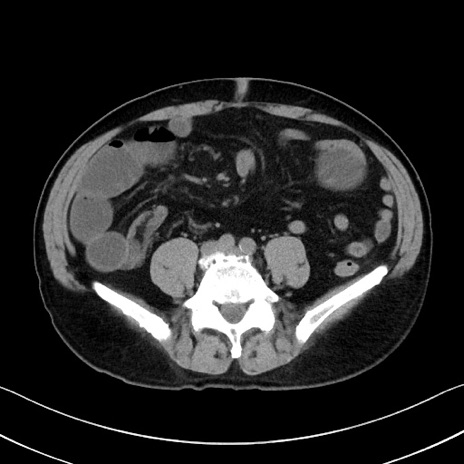

症例35(横断像)

【症例】70歳代 男性

【主訴】腹部膨満、嘔吐

【現病歴】昨日より腹部膨満感出現。本日増悪し、仙痛出現。嘔吐あり、受診。

【既往歴】糖尿病、胆摘後

【身体所見】BP 149/80mmHg、HR 74/min、BT 35.9℃、腹部:膨満、軟、圧痛なし。腸雑音減弱あり。上腹部正中切開瘢痕あり。

【データ】WBC 13500、CRP 1.72